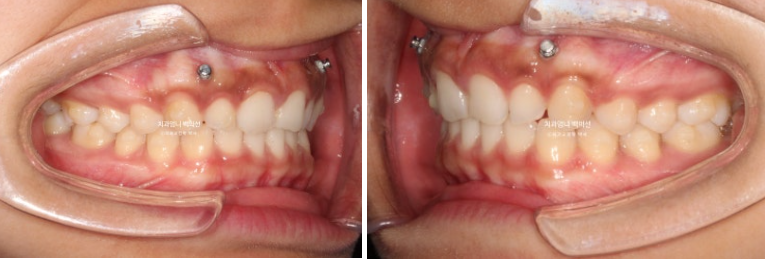

안모 비교 보겠습니다.

24.03~25.01

거미스마일은 많이 개선이 되었습니다.

앞니가 뒤로 쓰러져 있던 옥니도 상당히 개선되었습니다.

10개월의 치료기간 동안 치근흡수는 없으며 치근평행도는 양호합니다.

아래앞니과 위 앞니의 상당량의 함입이 눈에 띕니다. 위아래 앞니가 2mm씩 함입되었습니다.

덕분에 입술은 처음보다 좀 더 편하게 다물리게 되었습니다.